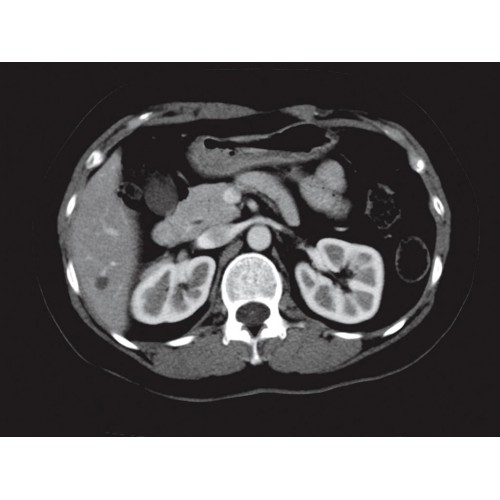

Современный 32-срезовый компьютерный томограф для точной диагностики. Обеспечивает высокое качество изображения при сниженной лучевой нагрузке. Удобный и надежный в эксплуатации. Подходит для широкого спектра диагностических исследований.

Компьютерный томограф GE Brivo CT385 представляет собой современное диагностическое оборудование, сочетающее высокую точность исследований с повышенным комфортом для пациентов. Этот аппарат открывает новые возможности для детальной визуализации анатомических структур.

Позволяет проводить комплексные исследования всех анатомических зон, включая нейровизуализацию, ангиографию, исследования органов грудной и брюшной полости. Особенно эффективен для раннего выявления онкологических заболеваний.